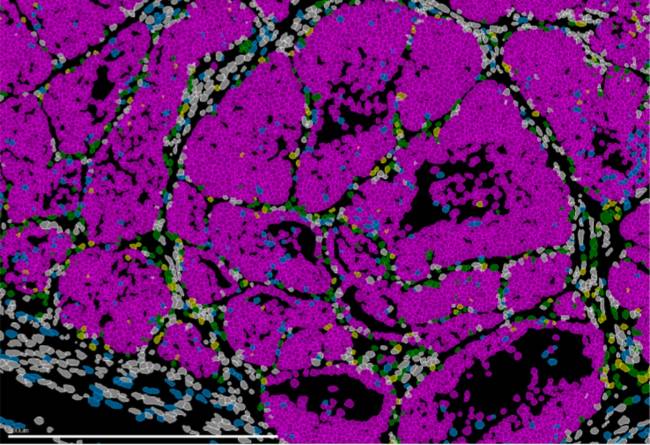

La rapamicina inhibe la actividad de mTOR

La rapamicina inhibe la actividad de mTOR en muestras de hígado de ratones con telómeros largos, pero no en ratones con telómeros cortos. / CNIO